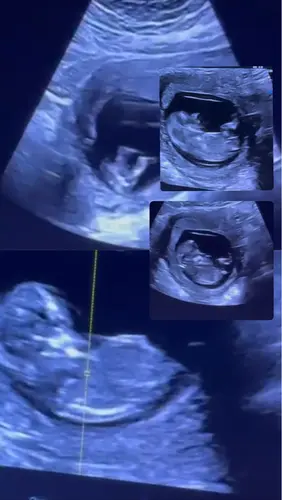

Wellicht dat ik hier tussen kom haha.. ziet iemand wat het is?😂

3 weken geleden